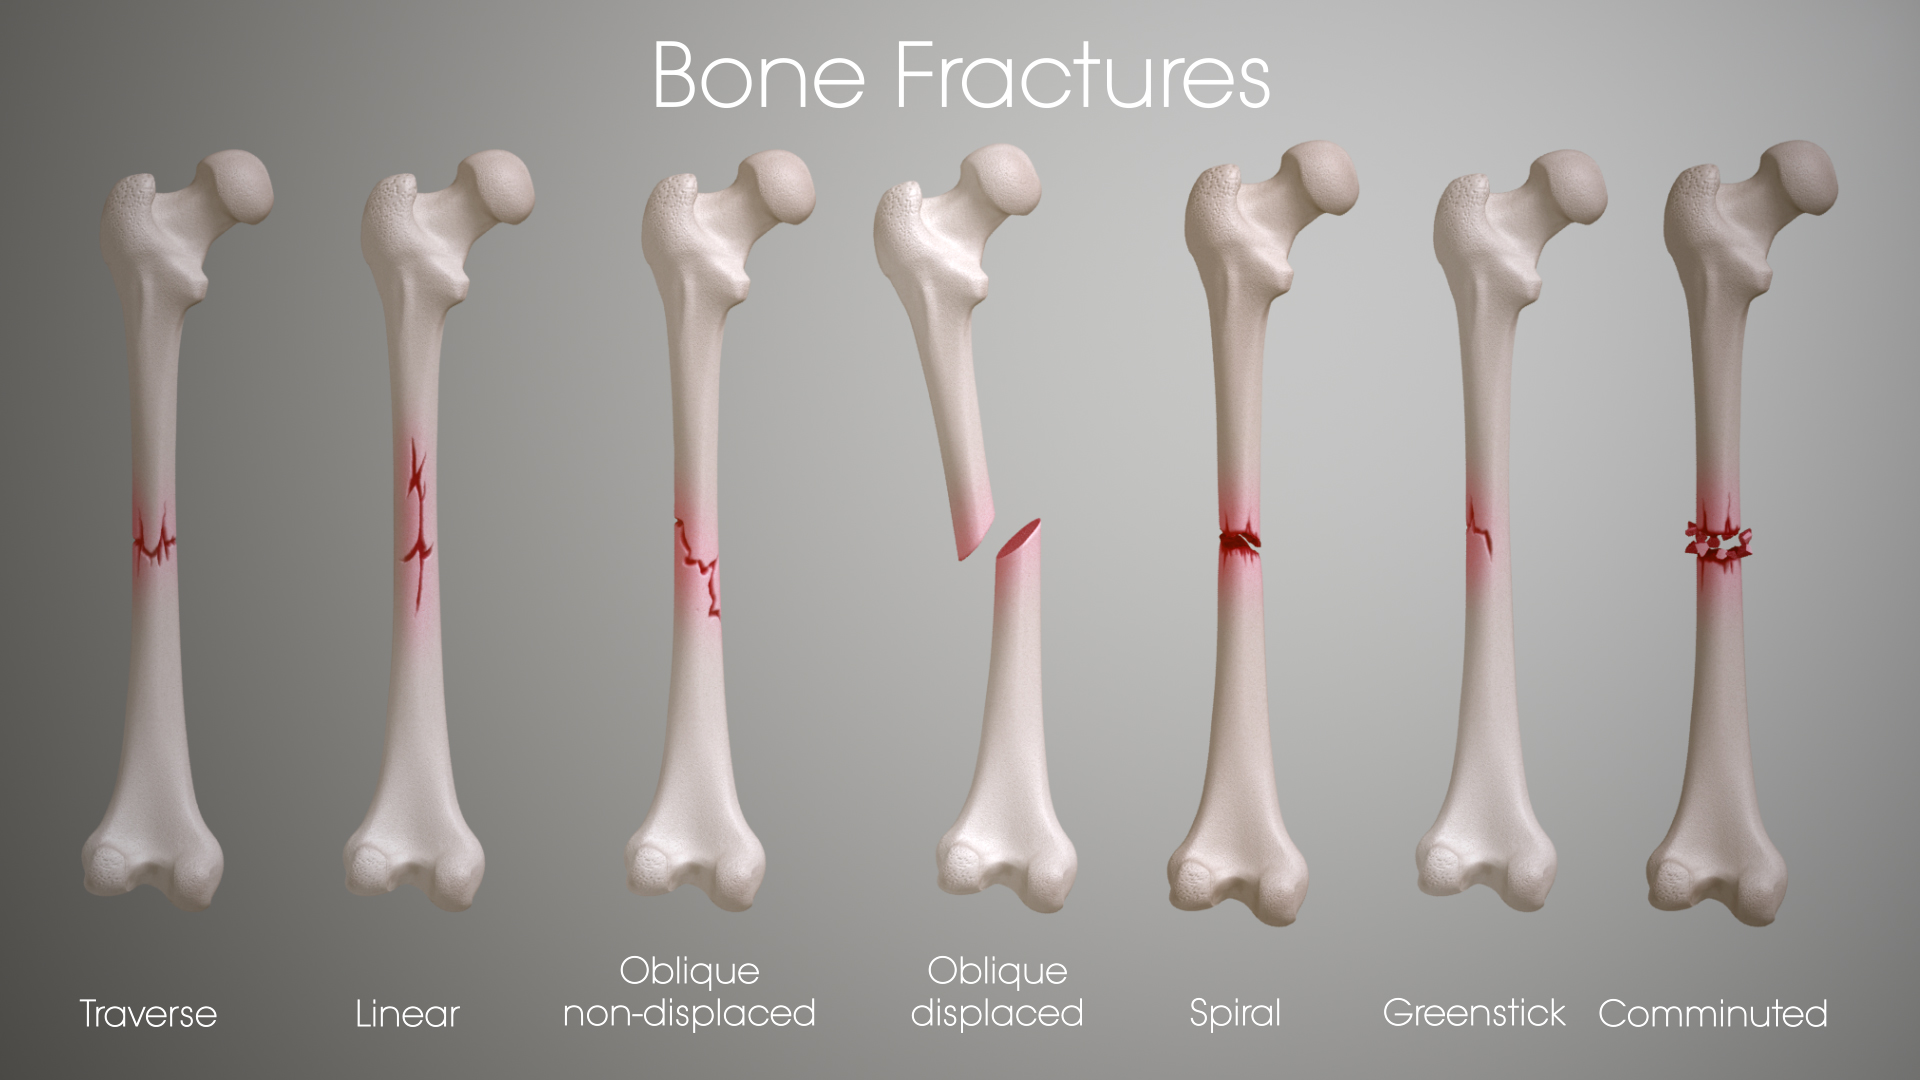

Fractures range from small partial cracks to complete breaks and can occur in any bone.

fracture In more severe cases, the bone may be broken into several fragments, known as a comminuted fracture. Overuse or repetitive motions can cause stress fractures. Fracture d�une porte, d�une serrure. Extends all the way across the bone (most common) transverse fracture: A fracture is a break in the continuity of a bone. An attorney intending on climbing the career ladder toward success finds an unlikely opponent in a manipulative criminal he. Rita riportò due fratture nell�incidente. Fractures usually fall within a set number of patterns.